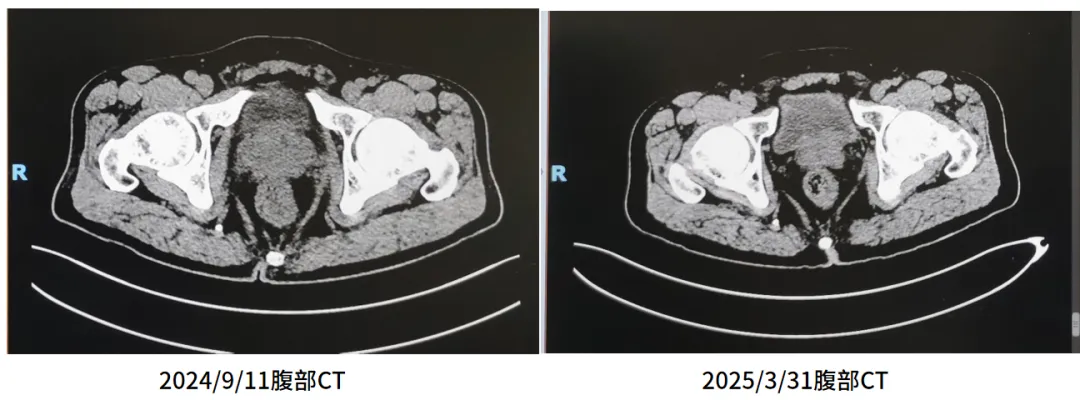

用药6个月后复查腹部CT

戈舍瑞林+恩扎卢胺治疗6个月后,2025/3/31复查腹部CT:对比2024-09-11前片示:1.临床提示前列腺恶性肿瘤治疗后复查,前列腺较前减小。2.右肺中下叶斑片影已吸收好转。3.右肺少许小结节,较前大致相仿。4.原气管内附壁黏液栓已基本吸收。

6.png